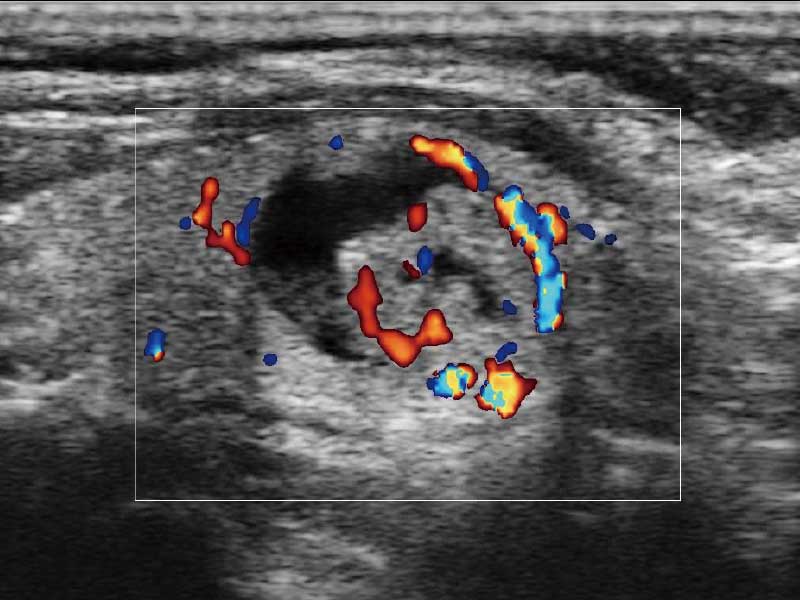

临床图